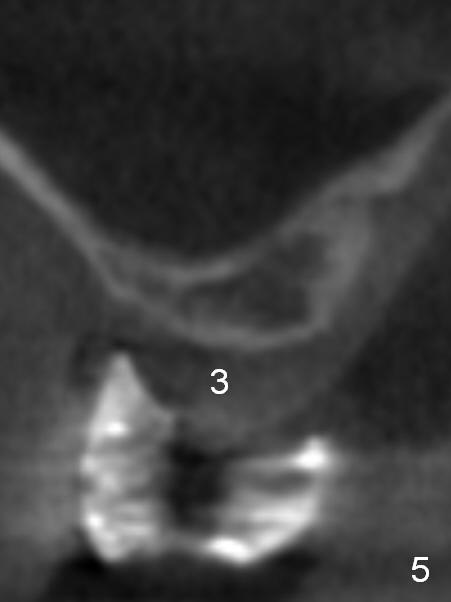

A 49-year-old lady has lost #2-4 for quite a while (Fig.1, no indication for antibiotic study (for cases with <6 months post extraction)). Bone height at #2 and 3 is limited. Use a 2 mm pilot drill to start osteotomy with rubber stopper at 4 mm, followed by insertion of 2 short parallel pins (PP) at #2 and 3 (Fig.2,4,6,8). The PPs may be not stable because of shortness. At #4 (8 mm initially), insert a marked PP for PA. If the position and trajectory of each osteotomy is correct, use trephine burs for further osteotomy at #2,3, since they have labels of 2,4,6 mm. For example small one at 4 mm, larger one at 6 mm. If the bone stays in place after trephine bur usage, use Bicon osteotomes to do sinus lift. Allograft and Osteogen is to be loaded in small syringes (x4). Previous implant surgeries indicate that the bone density of the maxilla is high (1,2). CT shows variable density (compare Fig.1 vs. 2, 3 vs. 4 et al). The density at the medulla is low; that at the cortices high. The patient plans to have 2 implants. If the implant at #3 is not stable, the implant at #2 will be needed for splinting.